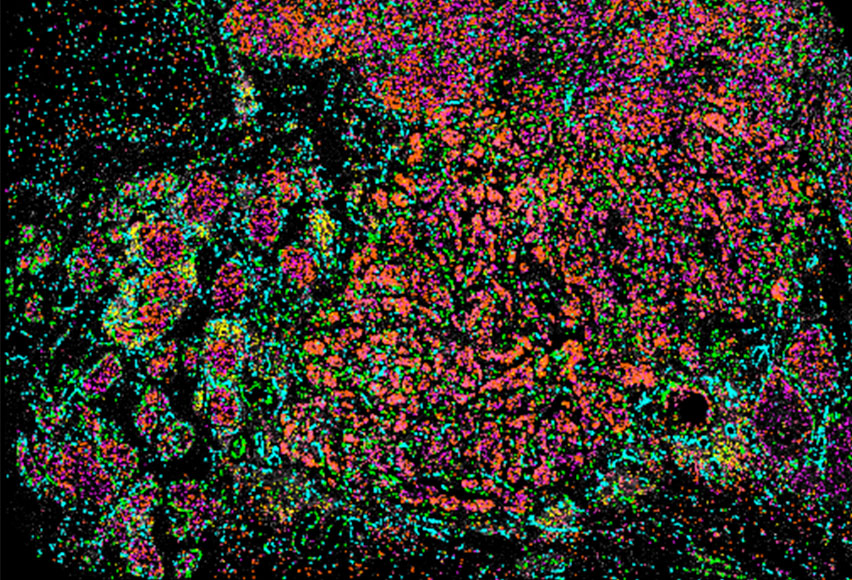

新型RNA原位测序

InSituVision原位自动化系统

泛癌种Cell Marker Panel